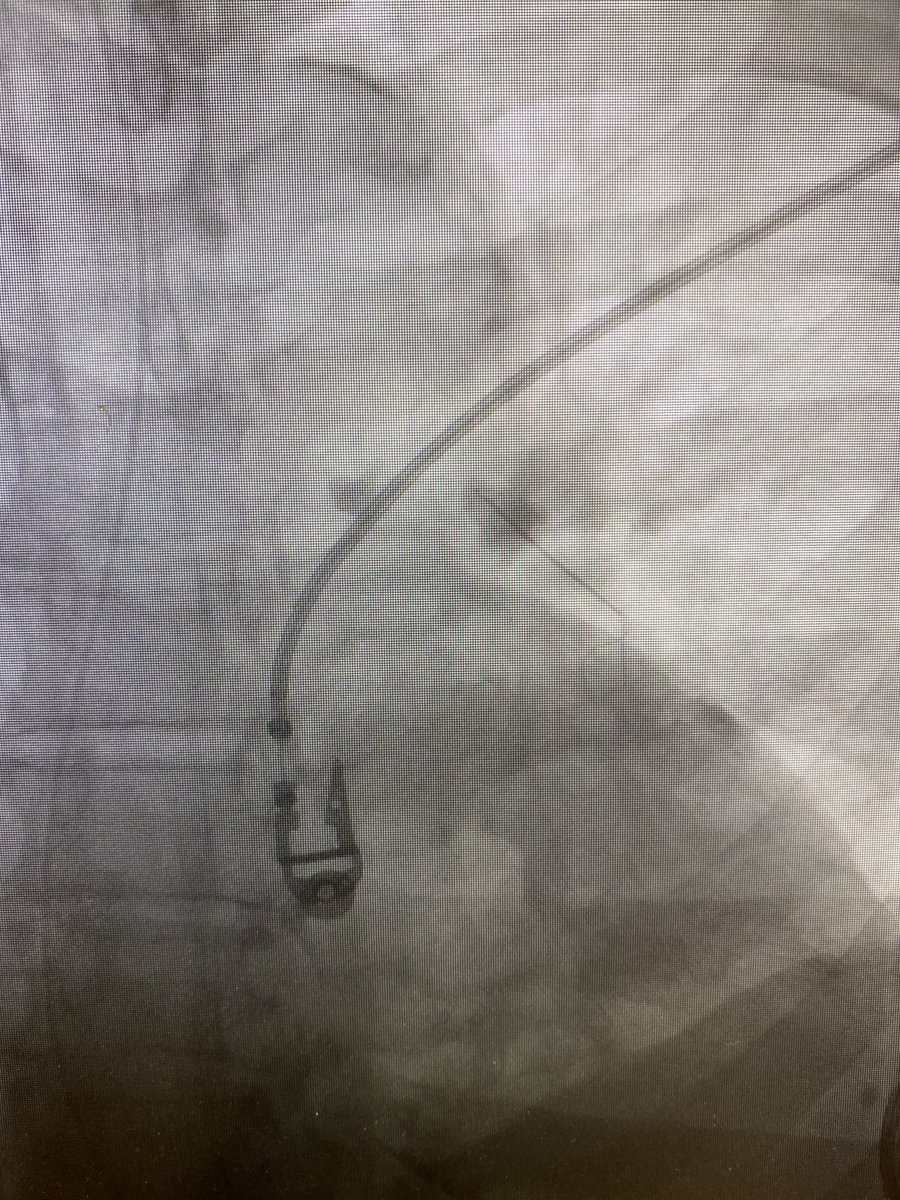

Fractured #filterOUT that was a bit harrowing; completely fractured struts in left PA and AORTA! Oh, and an extracaval apex...@rkryu @TheRealDoctorOs